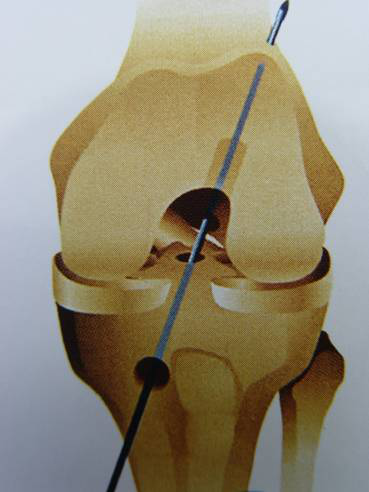

脛骨點選取

股骨點

1.準確定位,建立骨隧道。